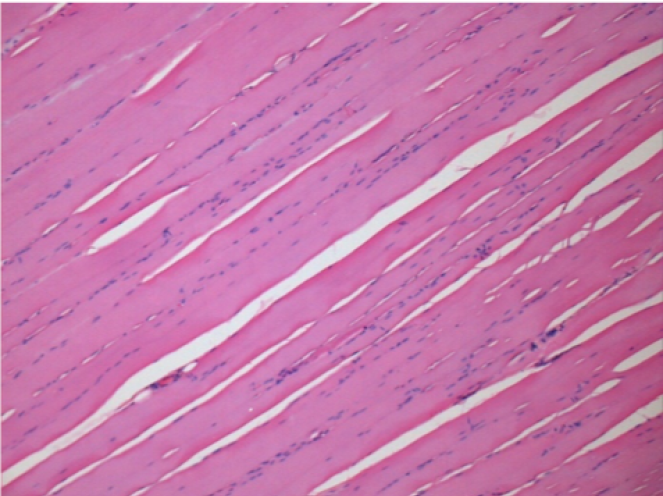

7 months (D210)after Endopeel IM Injection 0.1ml in the right pretibial muscle.

Complete Restitutio ad integrum after 7 months